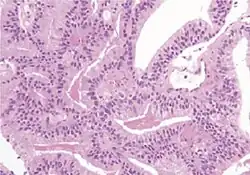

Microscopic characteristics

- Specific but relatively rare

- [notes 4]

- Collagenous micronodules[4]

- Glomerulations,[4] epithelial proliferations into one or more gland lumina, typically a cribriform tuft with a single attachment to the gland wall.[18]

- Perineural invasion.[4] It should be circumferential[18][notes 5]

- Angiolymphatic invasion[4]

- Extraprostatic extension [4]

- Relatively common and highly specific

- [4]

- Multiple nucleoli

- Eccentric nucleoli[4]

- Less specific findings.

- Mitoses (also seen in for example high-grade prostatic intraepithelial neoplasia (HGPIN) and prostate inflammation).[4]

- Prominent nucleoli[4]

- Intraluminal eosinophilic secretion[4]

- Intraluminal blue mucin[4]

In uncertain cases, a diagnosis of malignancy can be discarded by immunohistochemical detection of basal cells.[4]